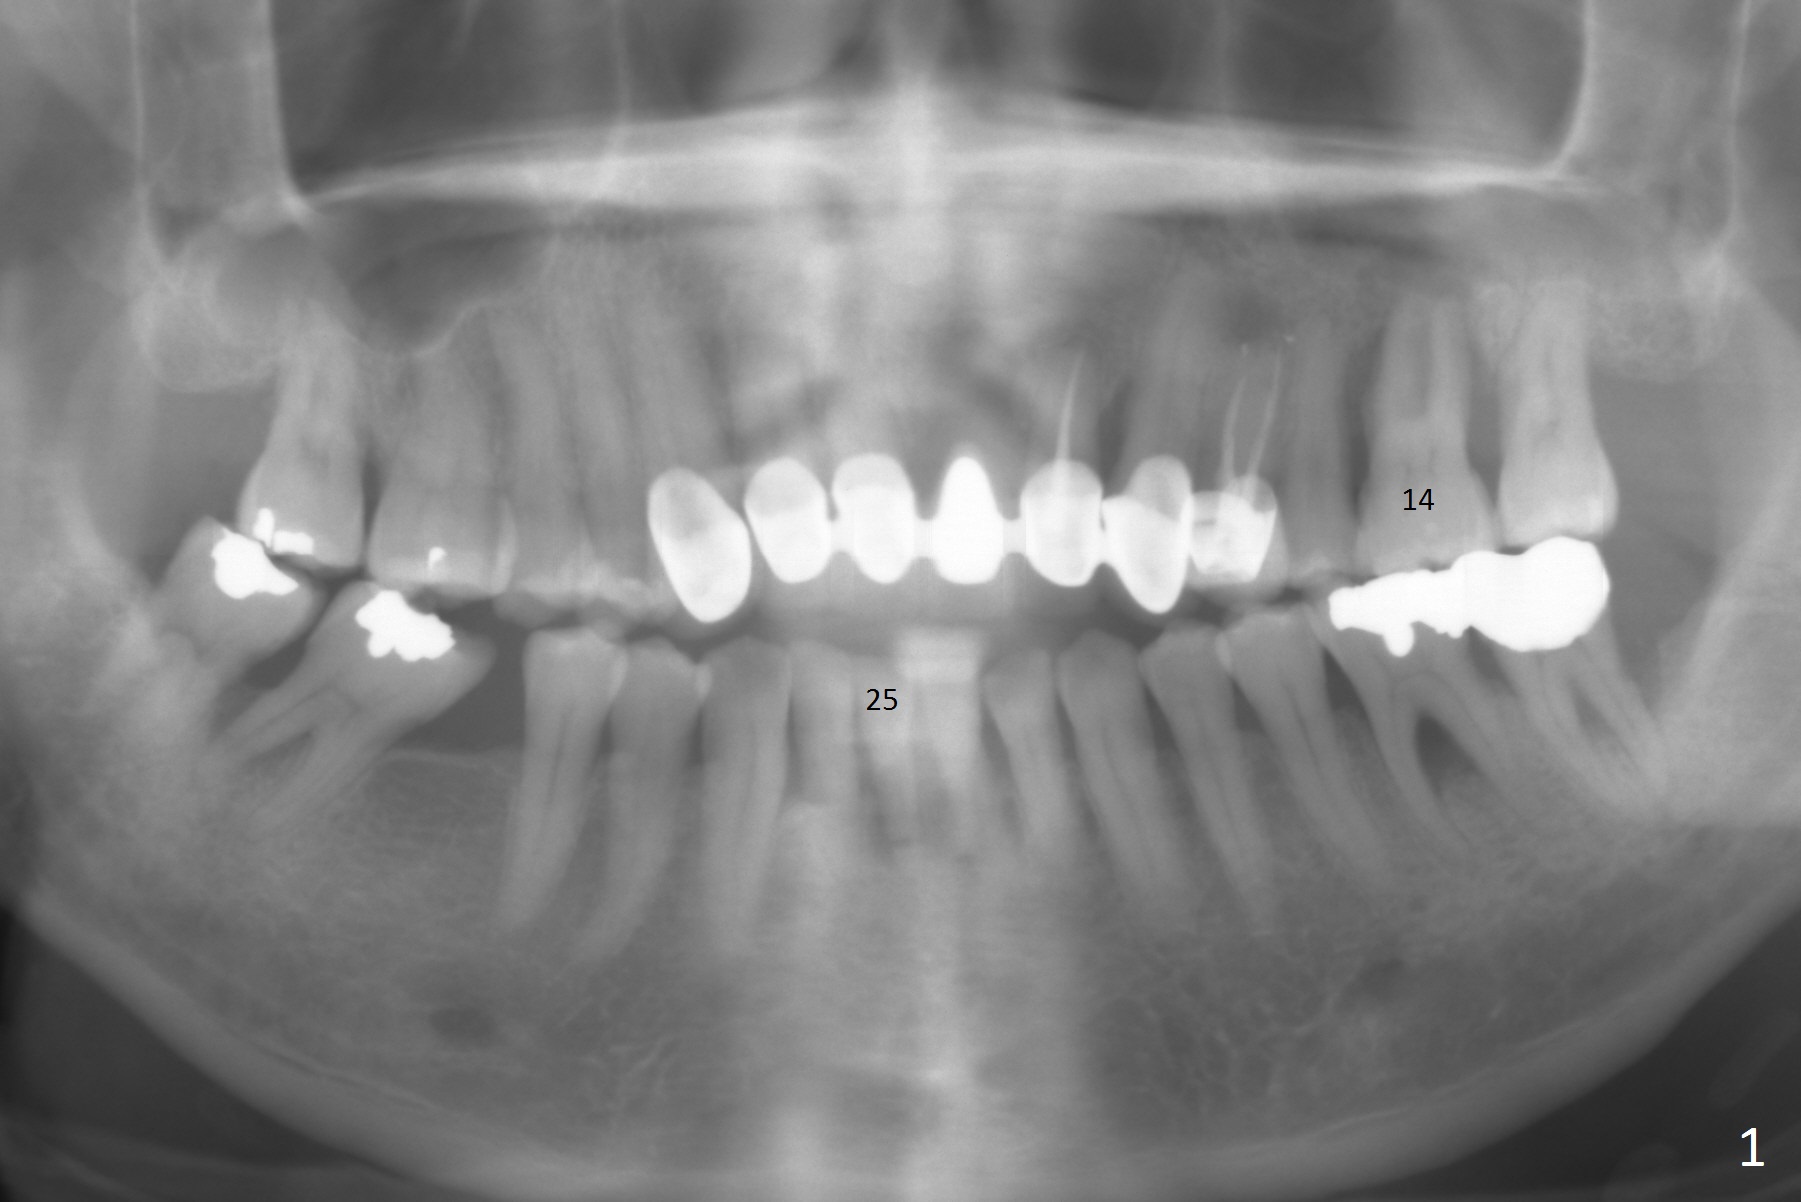

A 48-year-old man is determined to have implants for mobile teeth #14 and 25 (Fig.1). He is not pleased with the upper anterior FPD because of difficulty in cleaning. In addition to severe gingival recession (Fig.2), there is an abscess lingual to the tooth #25 (Fig.3). The latter should be associated with lingual plate defect. Osteotomy should be initiated in the center of the socket, in contrast to usual lingual starting point. A 3x16(4) mm 1-piece implant is to be placed unless the socket is small buccolingually or mesiodistally. Take PA immediately after his arrival for surgery to determine the mesiodistal width and the gingival thickness. The 2nd parameter will decide what parameter of the implant?

This patient is pleased to learn that an immediate provisional will be fabricated. The anterior open bite (Fig.2) will make the job easier.